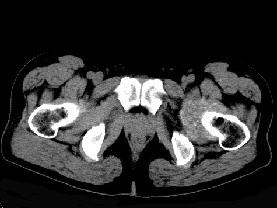

问题 男,56岁,因左髋关节疼痛、无外伤史,体检左髋关节稍肿胀,请结合所提供图像,选择最佳选项 ( )

选项 A、左髋关节滑膜炎 B、左髋关节类风湿关节炎 C、左髋关节退行性改变 D、左髋关节痛风 E、左髋关节滑膜骨软骨瘤病

答案 E